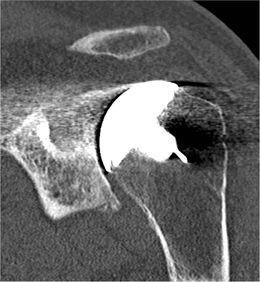

Radiographic assessment revealed periprosthetic radiolucencies as of the sixth post-operative week in 17 cases (Fig. 1) of which only one case was symptomatic and revised as mentioned above. This observation led the authors to collect computed tomography (CT) scans to screen for osteolysis in eight cases. On various slices in three planes, the observers found no evidence of bone loss that could lead to suspicions of early loosening; so we did not request CT for the 17 patients (Fig. 3).

Fig. 3

figure 3

On various slices in three planes, the observers found no evidence of bone loss that could lead to suspicions of early looseningᅟ

Radiographic assessment showed no signs of early migration, nor loosening over time at the longest follow-up of four years for the very first cases. However, periprosthetic radiolucent lines were observed at the upper zones in 17 shoulders. This led us to extend our investigation of early loosening by performing CT scans on eight patients. None of the CT scans revealed signs of loosening (Fig. 3).